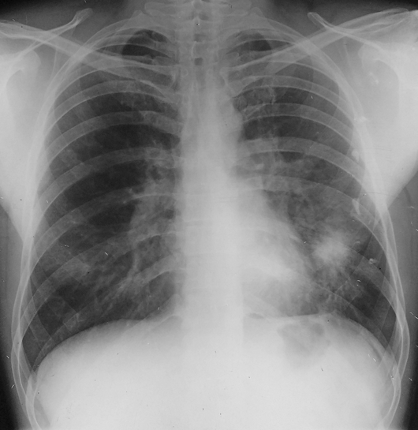

Rx toracică, incidență P-A

DESCRIERE:

pe tot teritoriul pulmonar, bilateral → opacități nodulare multiple de dimensiuni variabile, intensitate medie-mare, omogene, cu contur net

distribuție anarhică

blocuri adenopatice la niv. hilurilor pulmonare

DX: MTS pulmonare hematogene

DD:

hidatidoză - dimensiuni mai mari

bronhopneumonie - contur neregulat, neomogene, distribuție bazală